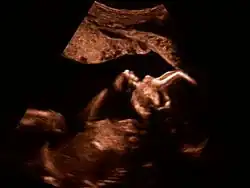

Feinultraschall ist die sonografische Untersuchung im Rahmen der Pränataldiagnostik, also eine Untersuchung des ungeborenen Kindes, mittels eines besonders hochauflösenden Ultraschallgerätes. Synonym werden die Ausdrücke sonografische Feindiagnostik, Organscreening und Fehlbildungsultraschall verwendet.

Der Feinultraschall kann etwa von der 19. bis zur 22. Schwangerschaftswoche durchgeführt werden. Man kann mit ihm einige Entwicklungsstörungen und einige körperliche Besonderheiten beim Kind feststellen bzw. mit einiger Wahrscheinlichkeit ausschließen.

Die Qualität und Aussagekraft der Ultraschallbilder hängt von vielen Faktoren ab, unter anderem von der Qualität der Untersuchungsgeräte (es gibt auch 3D-Ultraschall), der Fruchtwassermenge (wenig Fruchtwasser = schlechtere Schallleitung), der Kindslage (z. B. Schädellage), der Schwangerschaftswoche, der Stärke der Bauchdecke der Mutter (je fettleibiger sie ist, desto schlechter die Bilder), dem Vorhandensein von Narben etc. Je mehr Erfahrung der untersuchende Arzt hat, desto größer ist die Wahrscheinlichkeit einer richtigen Diagnose. Falsch-positive Diagnosen (Arzt diagnostiziert eine Auffälligkeit, die tatsächlich nicht vorhanden ist) können die werdenden Eltern erheblich psychisch belasten.[3]